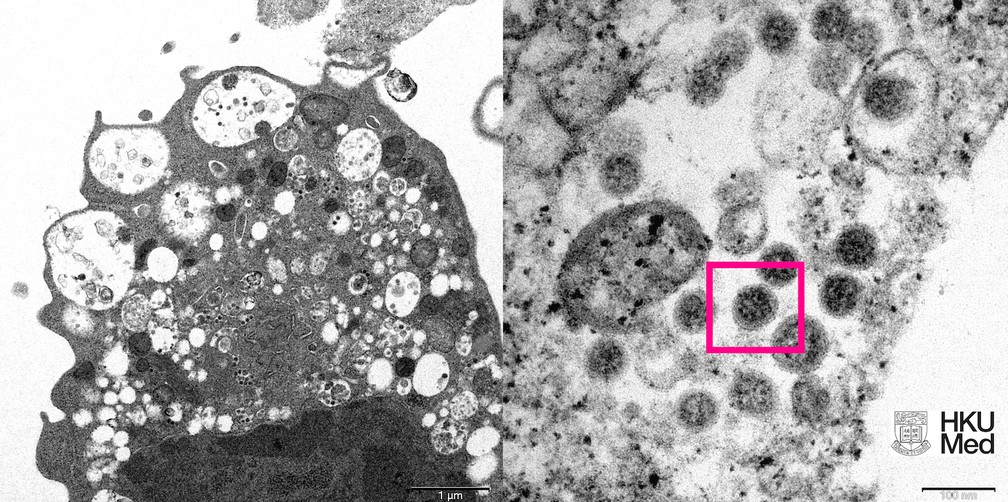

RS registra primeiras mortes decorrentes da variante Ômicron

Um homem e uma mulher, de 88 e 86 anos, são as primeiras mortes decorrentes da variante Ômicron do coronavírus registradas no Rio Grande do Sul, de acordo com a Secretaria Estadual de Saúde (SES). Em nota divulgada no final da tarde desta segunda-feira (17), a pasta informou que o idoso era residente do município de Sapiranga e, a idosa, de Progresso.

Os sintomas das vítimas tiveram início em 31 de dezembro e 1º de janeiro, e os óbitos ocorreram nos dias 2 e 5 de janeiro, respectivamente. Segundo a SES, ambos eram vacinados contra a covid-19 e possuíam comorbidades. Os exames que identificaram a variante foram realizados no Laboratório Central do Estado (Lacen/RS).

No total, o Rio Grande do Sul já identificou 264 casos confirmados ou sugestivos da nova cepa, distribuídos entre 46 municípios gaúchos. Desses, 21 foram confirmados por sequenciamento completo, método mais preciso pelo qual é feita a leitura de toda a cadeia genômica do vírus. Outros cinco apresentaram resultado indicativo para Ômicron por sequenciamento parcial do genoma do SARS-CoV-2.Outros 238 casos são considerados sugestivos: referem-se àquelas amostras que tiveram o diagnóstico pelo exame de RT-PCR que identifica parcialmente a variante ou que foram confirmados por serem de pessoas com sintomas e que tenham contato com casos sugestivos.

Identificada originalmente na África do Sul, a Ômicron é apontada como a responsável pelo súbito aumento de casos de covid-19 em vários países — o que também já foi percebido no RS nas últimas semanas. A SES ressalta que esses dados alertam para a importância de serem mantidas e reforçadas as medidas de prevenção: completar o esquema vacinal e fazer as doses de reforço, usar máscara e evitar aglomerações